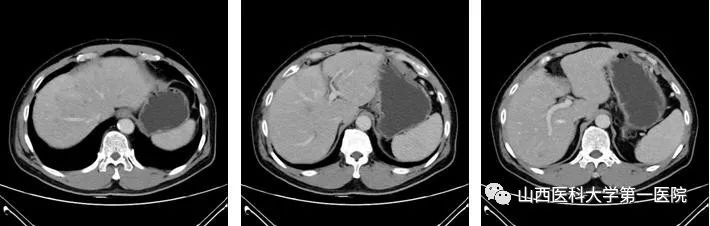

2022-08-26近期复查肝脏CT(静脉期)

该患者在团队成员仔细阅片、认真讨论下,因患者为PD-L1 CPS高表达人群,TMB-H基因状态,尽管目前国内外胰腺癌诊疗指南并没有对该类型患者指明个体化治疗策略,但我们通过查阅近年来已经报道的小样本临床研究以及个案报道资料,最终为患者制定了免疫联合化疗治疗策略(PD-1单抗+AG治疗6周期后,PD-1单抗+卡培他滨维持治疗),2022年8月26日,患者再次完善胸腹部CT评价疗效后,达到了大PR(部分缓解)的效果。多达20余处肝转移病灶几乎消失不见,患者可以正常工作生活。